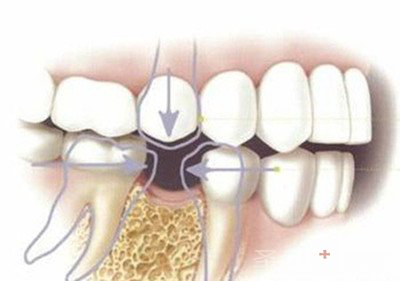

邻牙松动,再掉两颗:牙齿缺失位置形成的空缺会打乱本来整齐相互支撑、固定的牙齿状况,而缺牙导致邻牙失去了固定,相邻的两颗牙齿会向空缺位置倾斜,而且倾斜的情况是没有止境的,慢慢牙齿开始松动甚至脱落。

对牙伸长,再掉一颗:如果是下颌牙缺失,不仅是邻牙会倾斜,也会导致上颌牙失去了对咬牙,导致上颌牙向前伸长,严重的话会占据整个缺牙位置,到时候想要修复牙齿,连上颌牙也需要拔除才能修复。